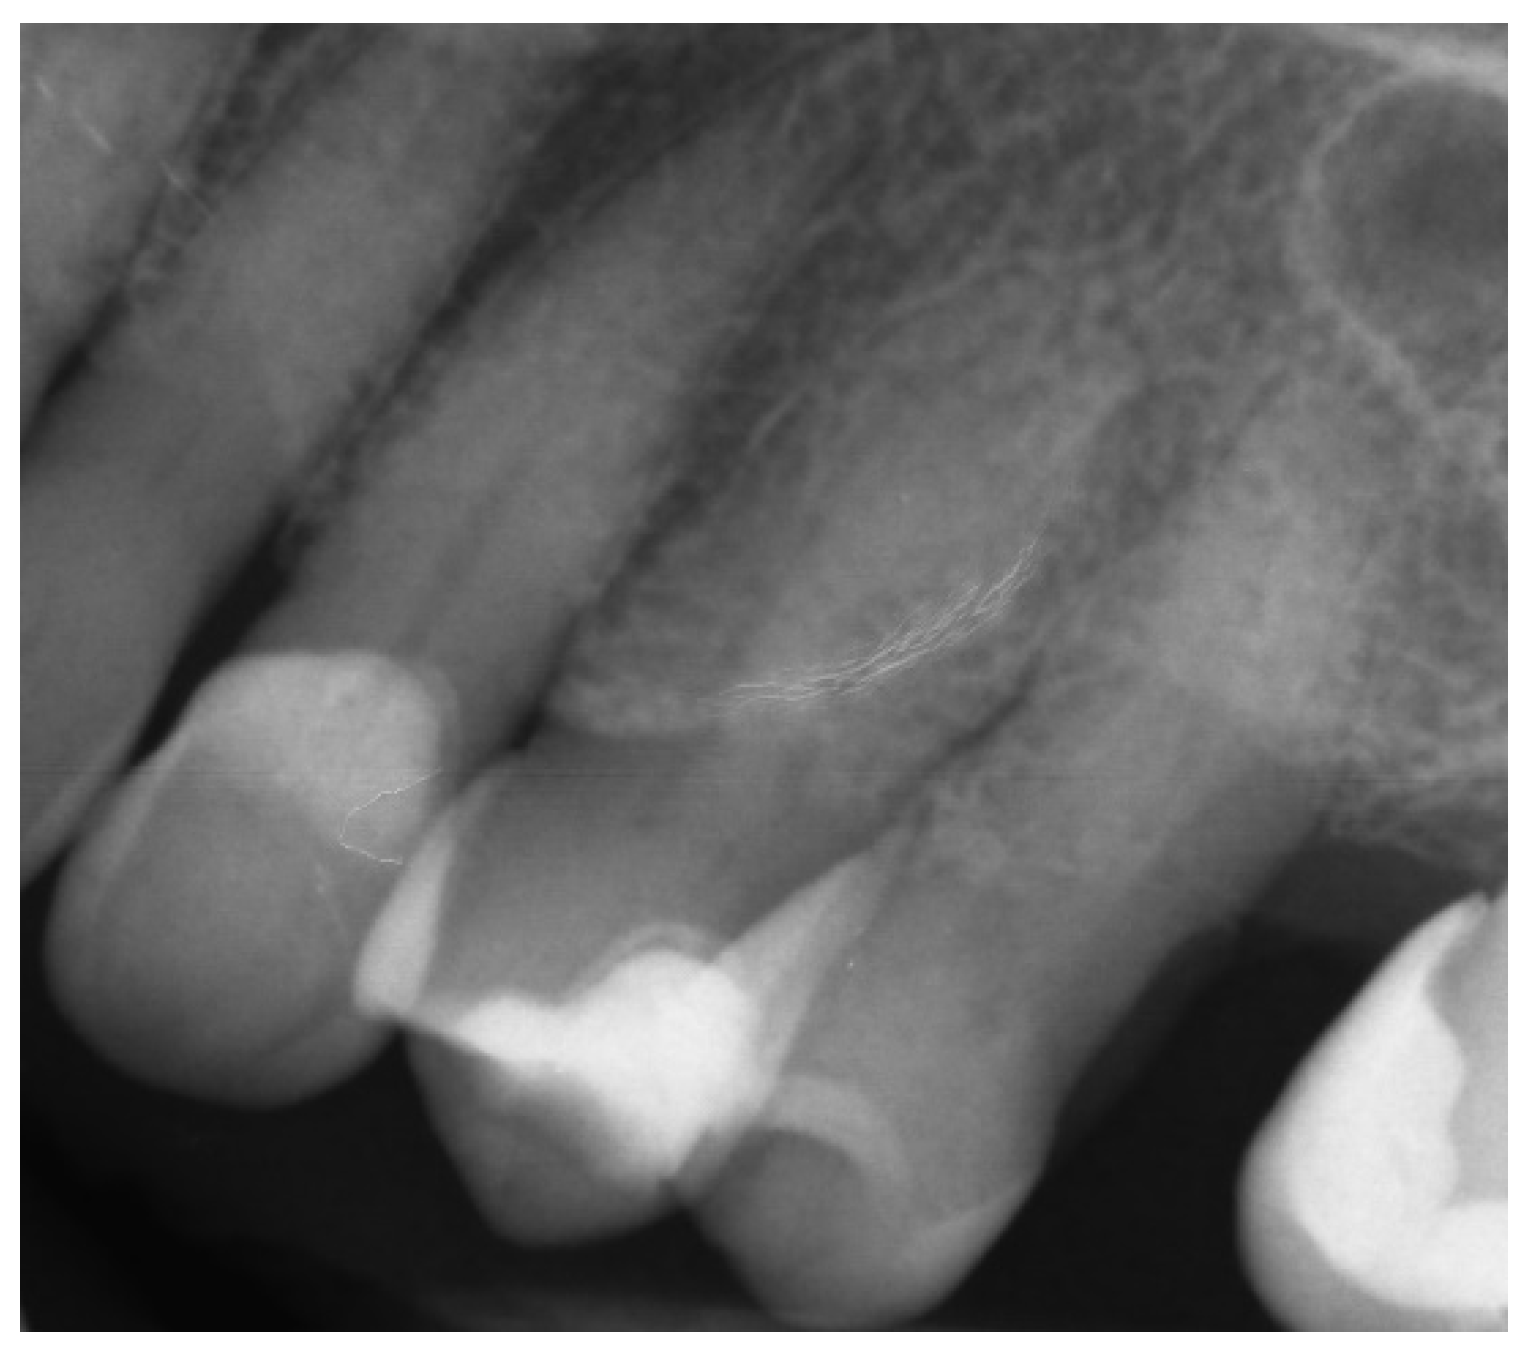

2.2.2. Case Report—Patient D: Symptomatic Pulp Necrosis with Pulp Canal Obliteration

A 68-year-old female patient reported to the endodontic specialist complaining of acute pain upon percussion of her maxillary first premolar (tooth 24), experienced for several days. The patient was healthy and did not have any general or chronic diseases. The clinical examination revealed tenderness to percussion and a negative response to the pulp sensibility test (cold test). Radiographic images revealed pulp canal calcification and the absence of the canal light (Figure 24). A CBCT scan was performed (CS 8100 3D, Carestream, 50 × 50 mm) and confirmed canal calcification (Figure 25). The palatal canal was found during the first visit. The buccal canal was obliterated. Due to the possible risk of higher tooth substance loss and perforation during endodontic access, we decided to perform the endodontic treatment with guided access.

Figure 24. X-ray image showing the obliteration of the root canal.

Figure 25. The CBCT image confirmed the calcification of the buccal canal.